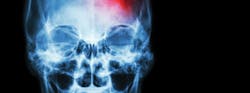

Stroke, or cerebrovascular accident (CVA), is caused by the sudden interruption of blood supply and oxygen to the brain. While 75% of those who suffer a stroke survive, 20% initially require some type of institutional care and 15% or more suffer permanent disabilities. This is because stroke almost always results in damage to brain tissue.

The most common type of stroke is ischemic stroke, which occurs when cerebral arterial blood flow is disrupted. Ischemic stroke may be caused either by a blood clot that forms in intracranial vessels (as a result of atherosclerosis) or by a clot that forms elsewhere in the body (in the heart, for example, as a result of atrial fibrillation) and then migrates to the brain. Since certain functions are linked to specific regions of the brain, the patient with ischemic stroke will display symptoms of changes in physical or mental status, based on the specific location in the brain where the ischemic damage occurred.

Stroke may also result from hemorrhage. Hemorrhagic stroke results from intracerebral and subarachnoid hemorrhage when bleeding occurs directly into brain and central nervous system tissues. Symptoms resulting from hemorrhagic stroke are more difficult to interpret and predict, since additional tissue trauma, resulting from increased intracranial pressure and edema, may exacerbate brain tissue damage caused by the initial hemorrhage.

It is critical to identify and diagnose the type of stroke involved before beginning treatment. Procedures intended to increase blood flow to parts of the brain affected by ischemic stroke may have catastrophic consequences for patients who have experienced hemorrhagic stroke. Regardless of its origin, stroke almost always results in brain tissue damage. Disabilities that result from a stroke are directly related to the extent and location of the damaged tissue. Right-side brain damage results in left-side paralysis, impaired cognitive function, impulsive behavior, memory deficits, and difficulty performing tasks. Left-side brain damage results in right-side paralysis, slow and disorganized behavior, memory deficits, and difficulty with language and speech. While normal function may return, patients who experience a stroke are frequently left with some sort of permanent disability.